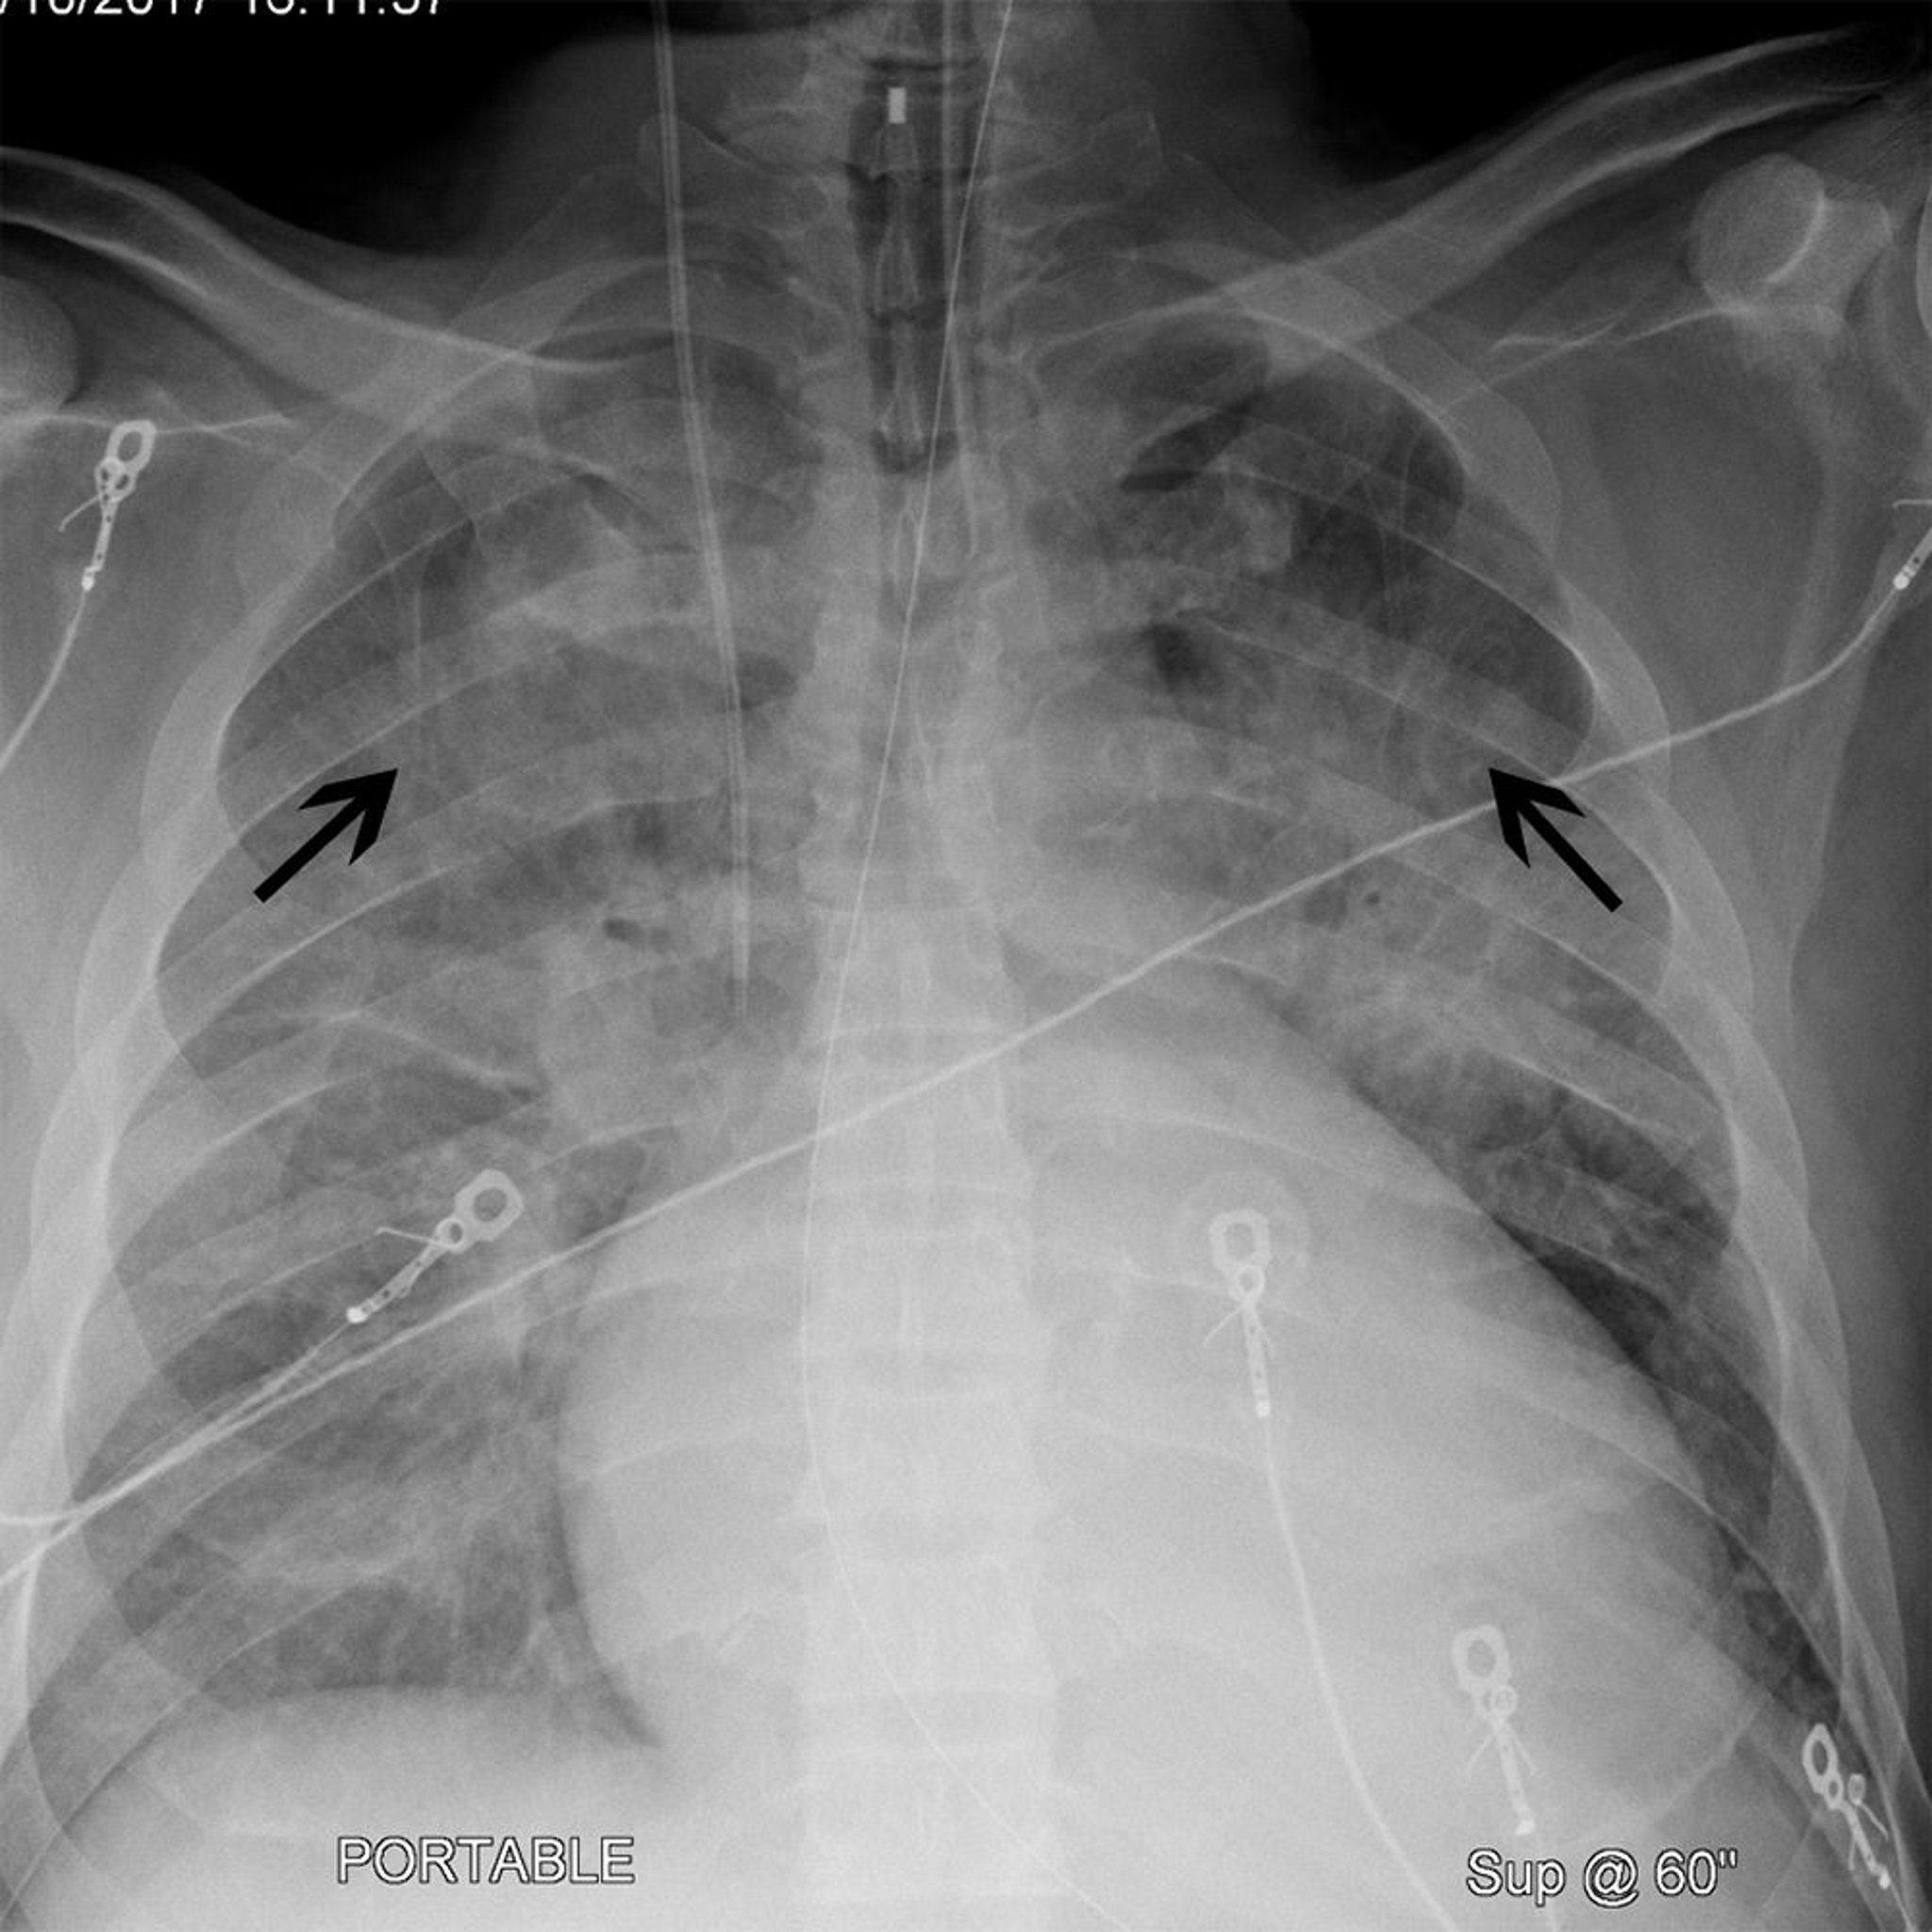

Рентгенограмма грудной клетки пациента с кардиомегалией и цефализацией

Этот пациент имеет кардиомегалию (ширина силуэта сердца составляет > 50% грудной клетки на передне-задней рентгенограмме грудной клетки). У пациента также имеется цефализация (черные стрелки), в результате чего легочные сосуды верхней доли становятся более заметными. Эти особенности часто наблюдаются у пациентов с сердечной недостаточностью.